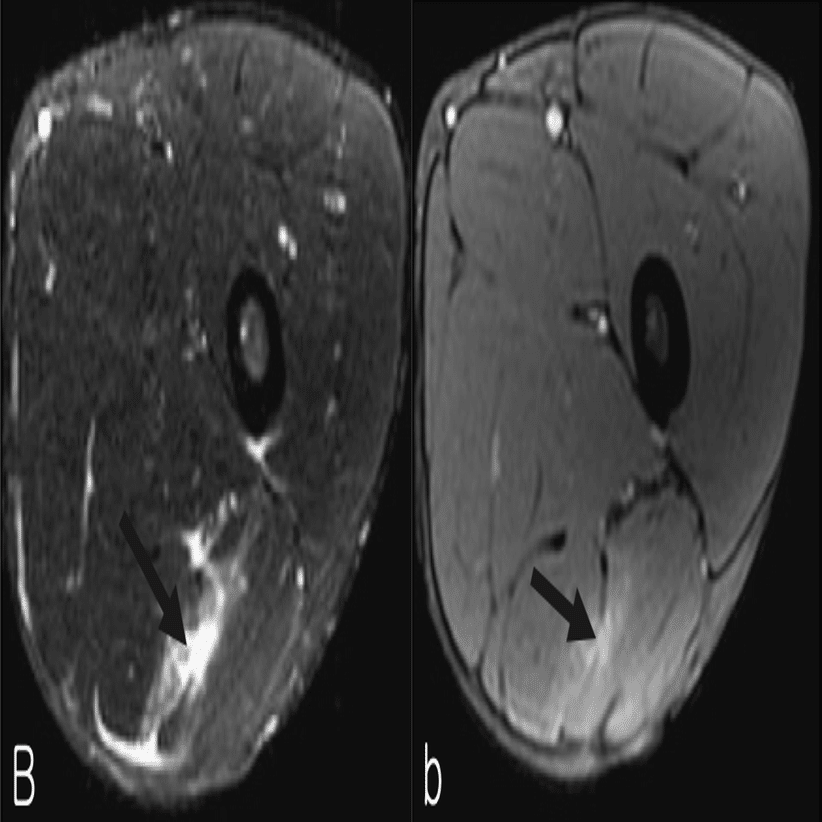

・Ⅱ型2度

(Pedret C, J Belg Soc Radiol. 2022から引用)

腱膜の連続性が背側部に途絶

(奥脇 透:大腿二頭筋肉ばなれの MRI 分類、臨床スポーツ、2019より引用)